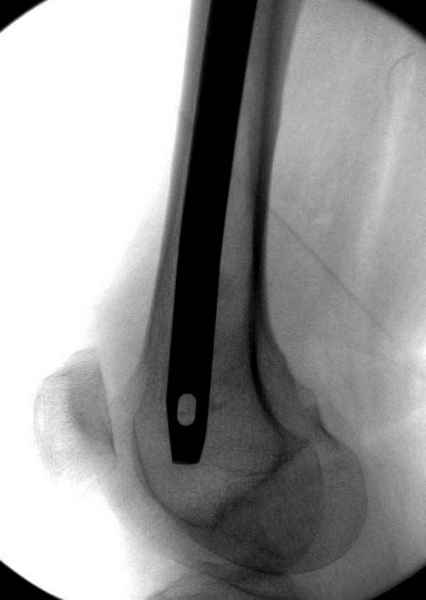

Наверное речь идет насчет parallel guide из набора. Применяем по возможности всегда, но,

как видно на снимке, не всегда получается

паралельно.

Такие несмещенные переломы обычно для молодых резидентов, и бывают технические неточности, но в этом случае посчитали фиксацию адекватной.

Соблюдая правила, многократными попытками можно

увеличить риск стрессового перелома латерального

кортекса.